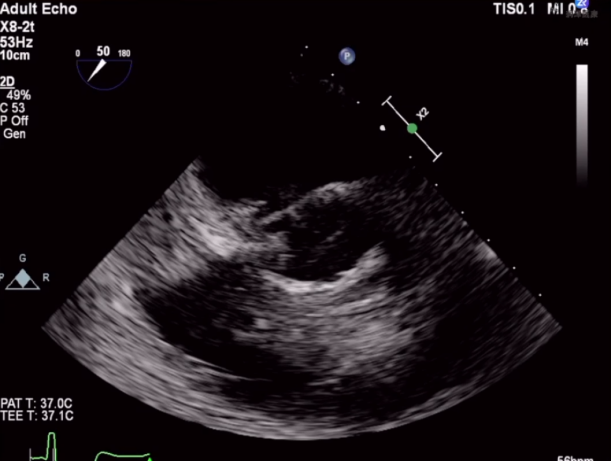

针对本例患者,术者团队介绍了特殊情况,食道超声检查示无冠窦窦壁有囊性结构,考虑存在感染,血流通过无冠窦窦壁喷射到囊腔里面,随后询问病史患者自述有泌尿系感染1月余,故考虑合并感染性心内膜炎,囊性结构是陈旧性赘生物。有专家认为患者有脑梗死病史2月余,系囊性赘生物脱落所致。

与会专家针对食道超声发现的囊性结构展开激烈探讨,对于泌尿系感染和脑梗死的病因认为是赘生物脱落所致,在此情况下,建议该患者不太适合TAVR手术。李飞教授同意现场探讨内容,下一步策略计划再次评估CTA,局部采血后血培养,核磁明确,考虑到患者心衰严重,首先保守治疗后,选择SAVR(外科主动脉瓣置换术)还是抗炎后TAVR具体情况深入分析后在做抉择。但有专家更倾向于外科开胸换瓣,可以进一步分析病理。